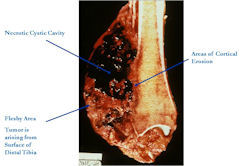

Gross Pathology

- Tumors are bulky, lobulated masses

- Have firm, soft, and hemorrhagic areas

- Dense sclerosis typical of a parosteal osteosarcoma and significant amounts of cartilage typical of a periosteal osteosarcoma is not common

- Cortex usually roughened and eroded

- There may be small foci of intramedullary invasion

Fig. 2 Gross Pathology of High Grade Surface Osteosarcoma of Distal Tibia